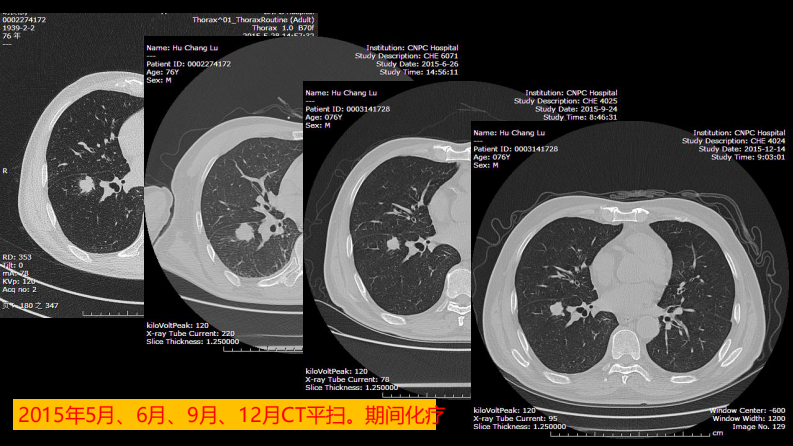

这例肺部病灶的比较影像学:价值评判.pdf